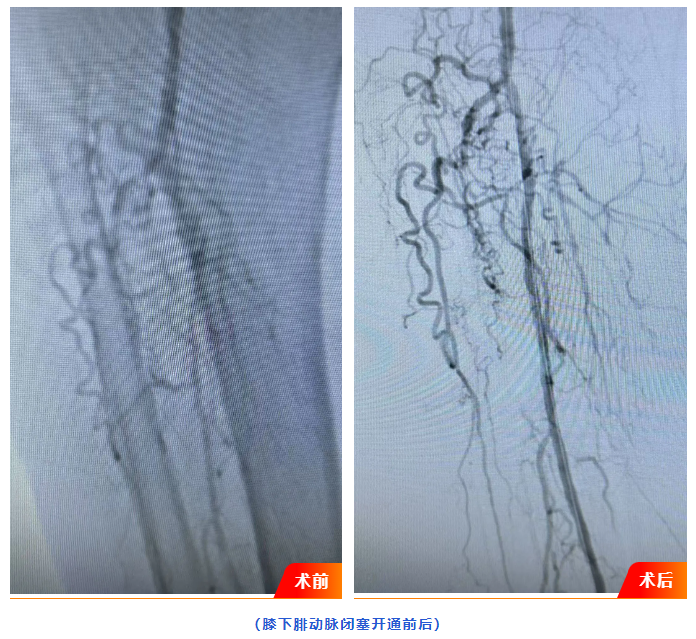

浏览量:1543月18日,广水一医院介入血管科成功为82岁高龄患者实施县域首例下肢动脉闭塞介入开通手术。此项手术的成功开展,填补了广水县域内血管介入治疗的技术空白,为周边地区下肢动脉疾病患者带来更高效、精准的诊疗选择。

患者刘某,82岁,3月13日因右下肢疼痛肿胀3月余入院,经下肢动脉CTA影像检查见其下肢动脉粥样硬化闭塞严重,同时合并右足趾骨皮肤湿性坏疽及谵妄症状,病情复杂危重。若不及时干预,患者将面临截肢甚至生命危险。

面对高龄、多系统并发症等挑战,广水一医院迅速启动多学科联合诊疗(MDT)机制,介入血管科联合内分泌科、骨科、神经内科等专家进行会诊,结合患者身体状况及影像学结果,最终确定为患者施行创伤小、恢复快的“下肢动脉闭塞介入开通”微创手术方案。

18日,介入血管科负责人刘自力及科室团队经右侧股动脉穿刺置入导管,利用球囊扩张成功开通患者闭塞的下肢动脉。术后患者右下肢疼痛、肿胀症状显著缓解。经观察,患者生命体征平稳,恢复良好,目前已顺利出院。

下肢动脉硬化闭塞症、糖尿病足是老年人常见病,传统治疗手段存在创伤大、恢复慢等局限。微创介入手术能以最小代价为患者重建血运,尤其适合高龄、基础疾病多的患者。目前,广水一医院已建立成熟的血管疾病诊疗体系,未来将持续推进技术创新与学科融合,为周边群众提供更优质的医疗服务。